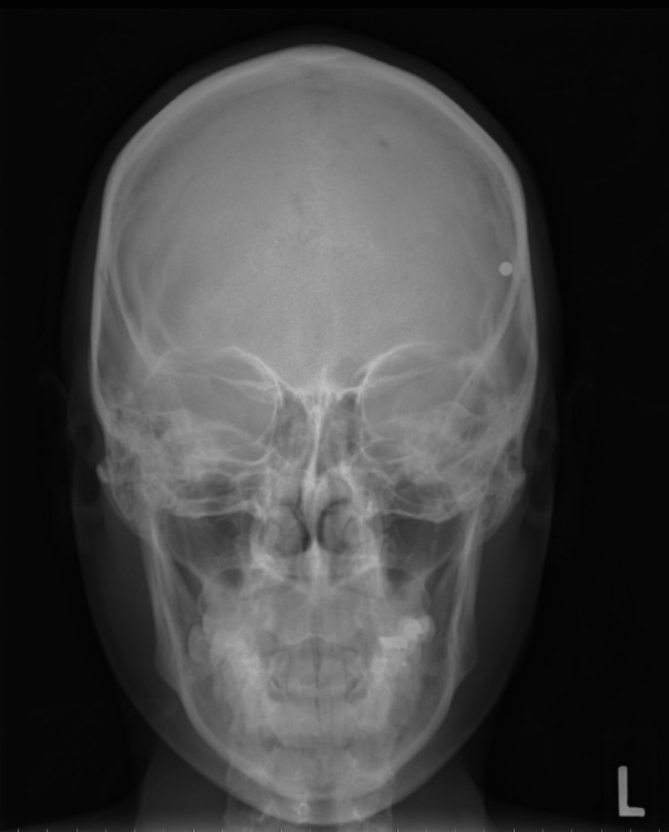

오늘은 BB탄 또는 총알등이 머리/두개골에 박혀있을 때 나오는 Xray 영상에 대해서 알아보겠습니다.

우선 Skull AP 영상 (똑바로 누운상태에서 앞에서 뒤로) 쵤영입니다. 거의 모든 촬영부위의 기본이 됩니다.

그림에서 보는 것과 사진의 우측 상부, 환자의 좌측 관자놀이 부근에 하얀색 금속음영이 아주 작은 원형으로 보이고 있습니다.

영상에서 상하좌우의 위치는 확인 할수 있지만, 어느정도의 깊이에 위치하는지는 파악이 어렵습니다. 예를 들면 앞 이마쪽에 있어도 나타날 수 있고 정측면에 있다면 두개골은 안쪽 뒤쪽에 위치한다면 후두부의 같은 선상에 표시 될 것이기 때문입니다.

BB bullet으로 알려져 있기 때문에 위치는 확인이 가능 했지만 Xray 사진의 경우 3차원적 위치를 확인하기 위해 추가적인 영상이 필요합니다. (최소 2매)

보통은 AP 전후방향상과 Lateral(Lat) 측면상으로 기본 구성이 됩니다. 물론 더 정확한 위치 파악을 위해서는 각도가 들어가는 Axial상(축방향) 또는 물체를 분리해서 보는 Tangential(접선상) 등이 추가 될 수도 있고, 물론 CT 3D 등을 이용하면 정확한 위치를 확인 할 수 있습니다. 총알의 금속 물질이 무엇인지 파악이 인된 상태이기 때문에 MRI는 금속 물질을 추적하는데 있어서 제한적으로 사용됩니다.

추가 됨 좌측 측면상(Lt lateral)에서 확인하면 총알의 위치는 약간 후두부 쪽에 있는것이 확인 가능 합니다.

각각의 한장씩의 사진에서는 평면상으로 겹쳐지는 부분이 표시가 되지 않지만, 최소 두장 이상의 영상이 있다면, 전후 방향의 위치와 측면방향의 위치 확인이 가능 하기 때문에 3차원적 위치추적이 가능하게 됩니다.

이와 같이 한장에서 확인 할수 있는 정보보다 전후 측면 두장의 사진의 조합으로는 더 많은 정보확인이 가능합니다.

오늘은 BB탄 등의 금속 물질이 Skull Xray 상에서 어떻게 나타나는지, 왜 두장 이상의 사진을 촬영하고 어떤식으로 위치파악을 하는지에 대해서 알아보았습니다.